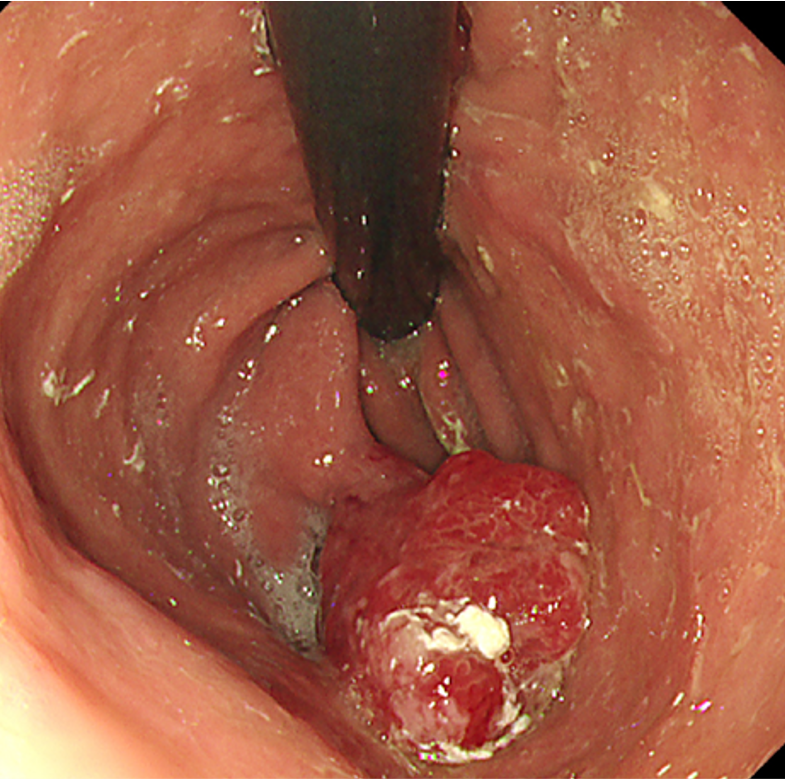

胃過形成性ポリープ